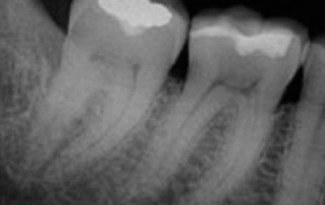

This emergency patient came to me after his four unit porcelain prosthesis had dislodged. It had been cemented with temporary cement. He had a closed bite with no overjet and I believe this was part of the reason (occlusal trauma) … Continue reading